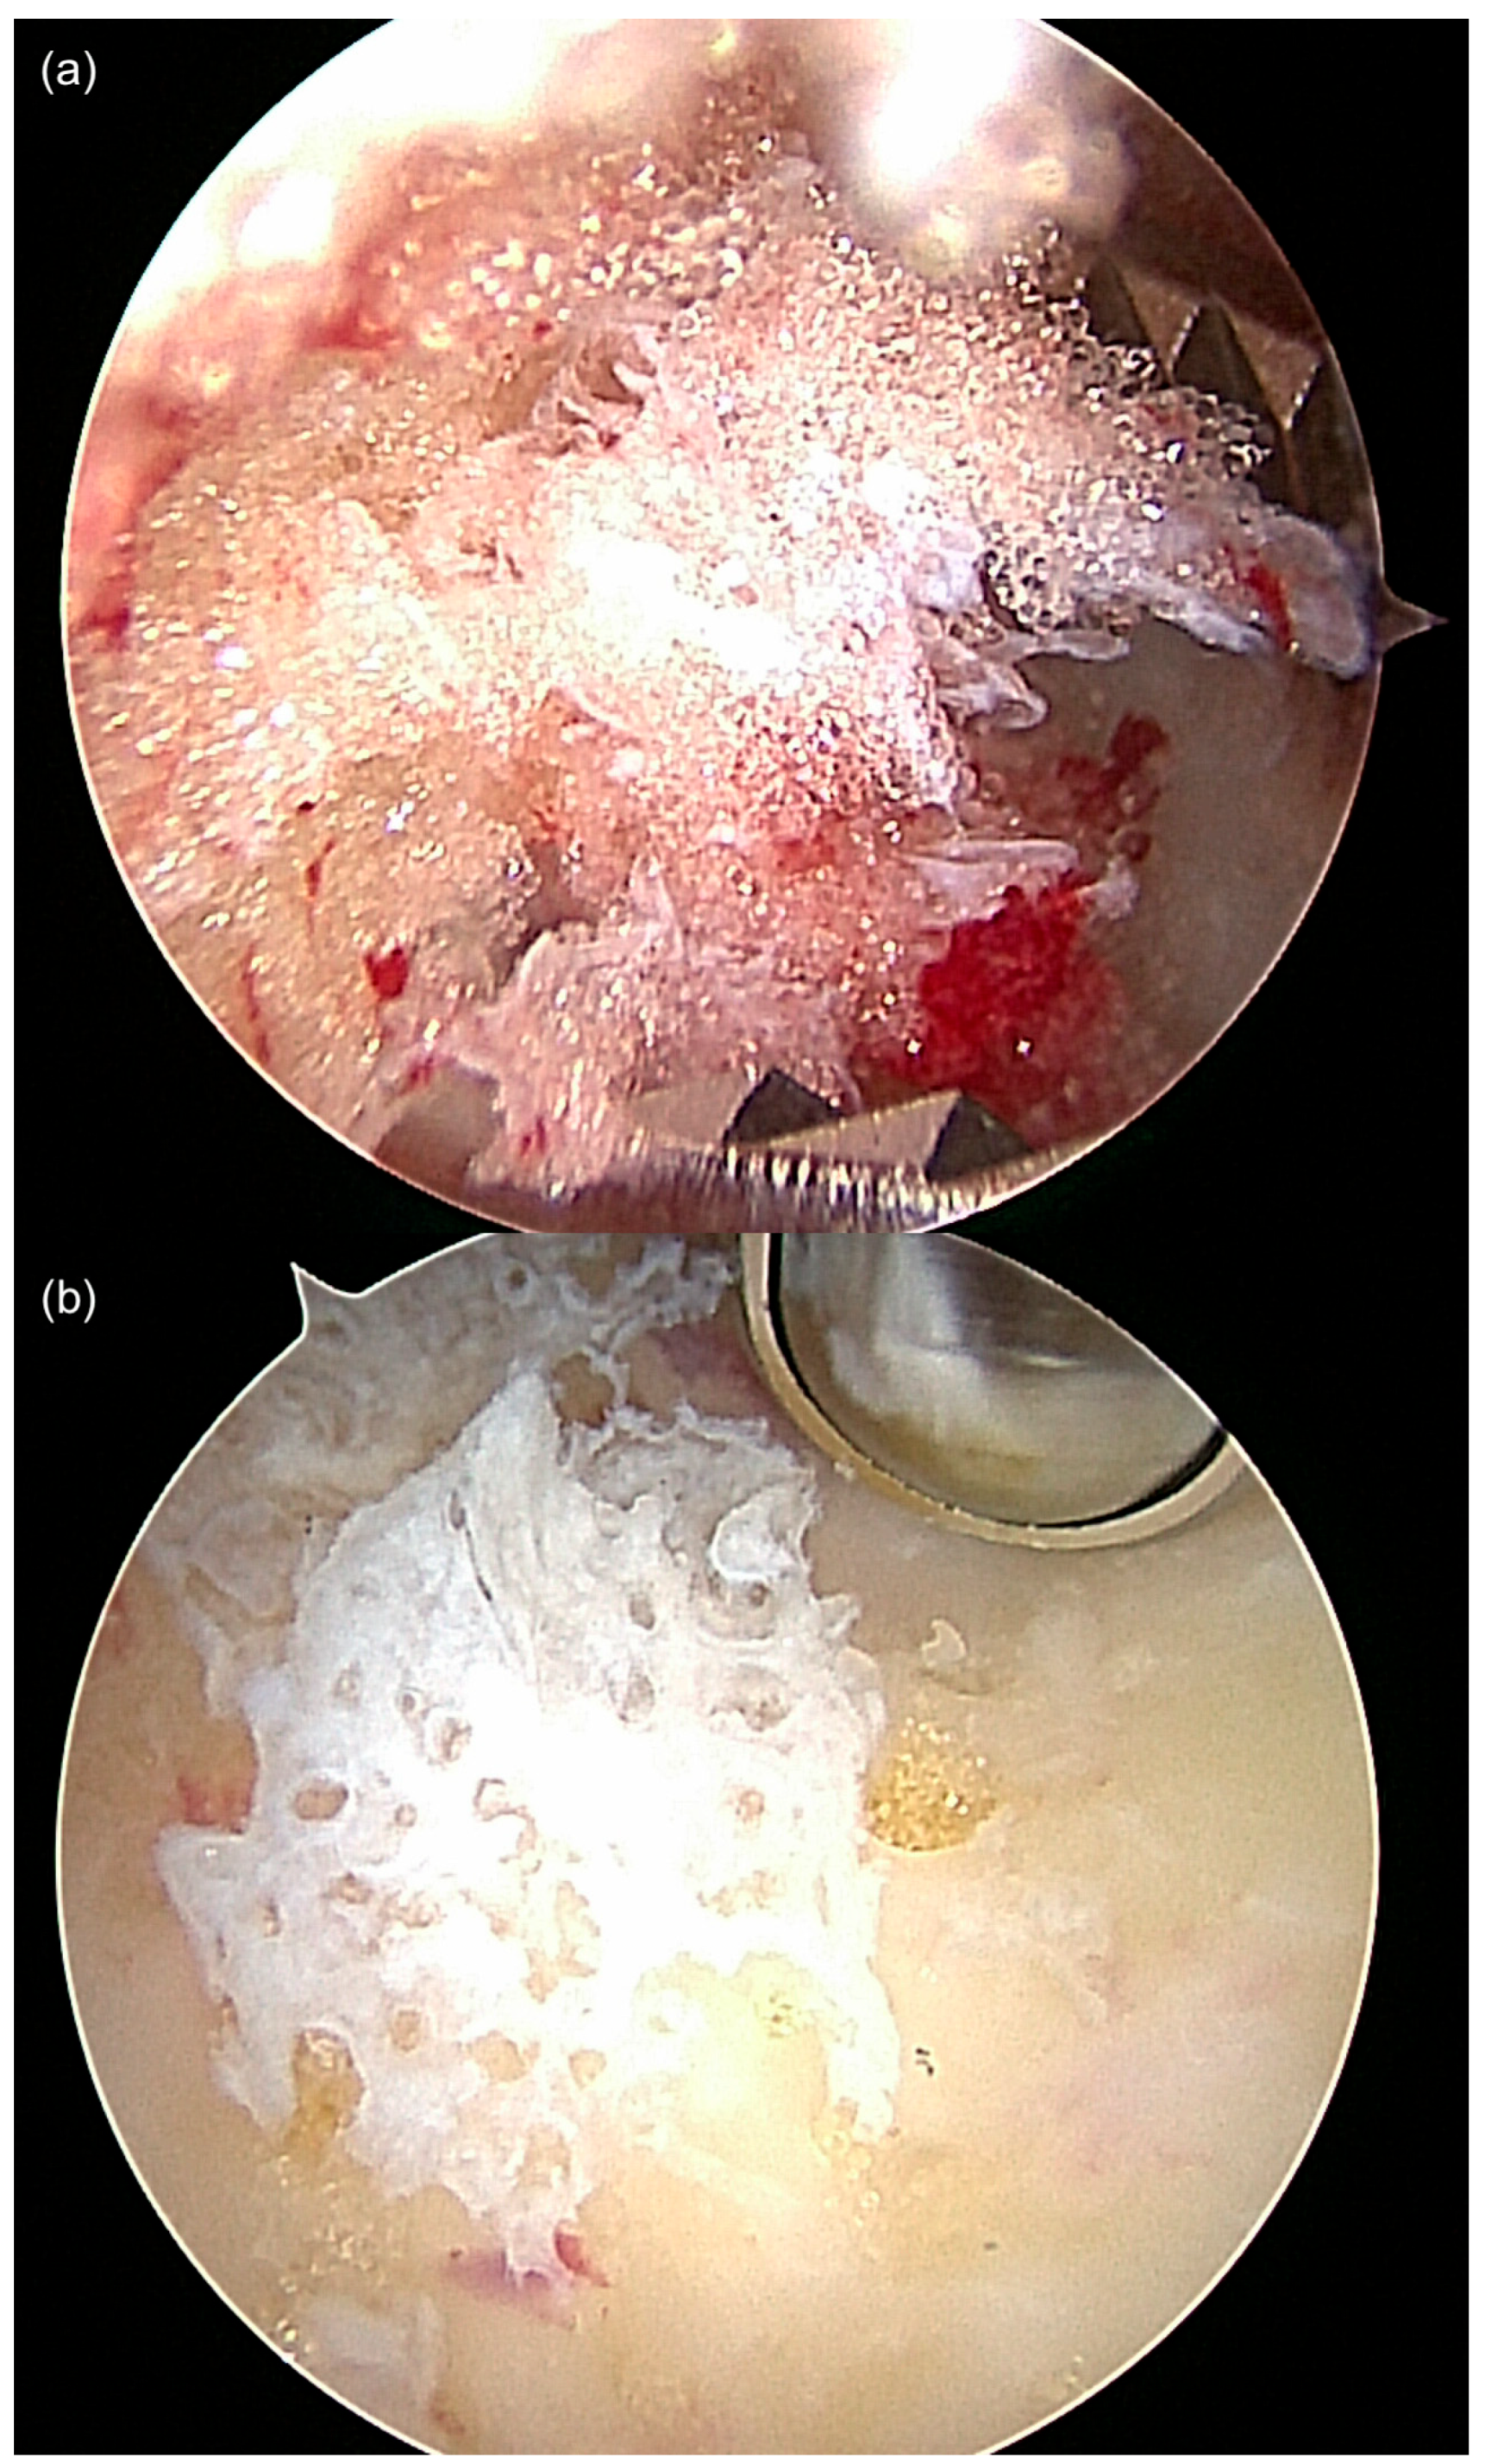

The surgical technique has been previously described by the authors [,,]. The type of anesthetic procedure was determined by the patient and the anesthesiologist. The patient was placed in a stable lateral position on a radiolucent table. The dimensions of the bone lesion were marked on the skin of the lateral rear foot with a sterile pen under fluoroscopic control. The two portals for ossoscopy were marked according to the size of the cystic bone lesion. A tourniquet was used to reduce bleeding into the bone cavity and to facilitate visualization. After skin incision and blunt dissection of the underlying soft tissue, the thinned-out cortex was penetrated with a semi-sharp obturator before introducing the sheath for a 2.7 or 4 mm scope into the cavity. During blunt dissection to the lateral wall of the calcaneal bone, care was taken not to harm the sural nerve and the peroneal tendons. Contrary to ossoscopy of the calcaneal bone for a simple bone cyst, clear vision of the bone cavity in IOL can only be achieved after a second portal has been established and thorough endoscopic irrigation has been performed. Therefore, loose lipomatous tissue was washed out, and the typical calcified areas of intraosseous lipoma became visible. The calcifications were cleaned out using an arthroscopic shaver, and larger pieces were grasped using an arthroscopic punch or grasper (Figure 2). Often, a tennisnet-like pseudo-membrane covered the walls of the cavity. This membrane is common for SBC but can also be present in calcaneal lipoma, suggesting their common etiology (Figure 3). The membrane was completely resected to prevent tumor recurrence. Any visible tumor tissue was completely removed and sent for histopathological analysis. Injection of radiopaque contrast medium verified the integrity of the bone cavity (no accidental damage and leakage) and helped determine the amount of injectable bone substitute needed to completely fill the lesion.

Figure 3.

Often, typical features of IOL ((a), fat tissue) and SBC ((b) membrane/cyst lining) were both observed in parallel in calcaneal ossocopy, suggesting a common pathogenesis and transitional forms of SBC and IOL. Both images are from the same ossoscopy (case 12).

Interestingly, two cases of IOL (cases 5 and 12) with characteristic preoperative MRI findings were histopathologically diagnosed as SBC. One additional case of MRI-diagnosed SBC showed membranous material with a histiocyte-resorptive reaction, consistent with SBC (case 11). Another case had material from a hemorrhaged lesion along with several bony particles (case 8), but no clear signs of lipoma of the bone. The absence of lipomatous tissue can be explained by the surgical technique. During endoscopic resection of IOL, the lipomatous tissue from the bone cavity is often washed out until a clear ossoscopic view is established and appropriate specimens are obtained (see Section 2.1). This problem was addressed later in the study (starting with case 13) by taking biopsies blindly once access to the tumorous lesion was established and prior to introduction of the scope. Our findings support the observation that SBCs can heal with fatty conversion of the cystic cavity, resulting in partly cystic remnants that may eventually transform to IOL (Figure 3). We agree with the findings of Tins at al. that at least part of the so-called IOLs are in fact, healed simple bone cysts [].

While MRI allows differentiation between cystic from lipomatous areas of the lesion, histopathological analysis is required to verify the correct diagnosis. Direct endoscopic visualization of the lesion can help to correctly assess mixed and transitional forms of SBC and IOL macroscopically (Figure 3). The high resolution of modern scopes (4K) and the magnification factor provide a much more detailed view of the findings during ossoscopy compared to open surgical resection. Thus, the tennis net-like membrane of SBC and other components of the lesion can clearly be identified.